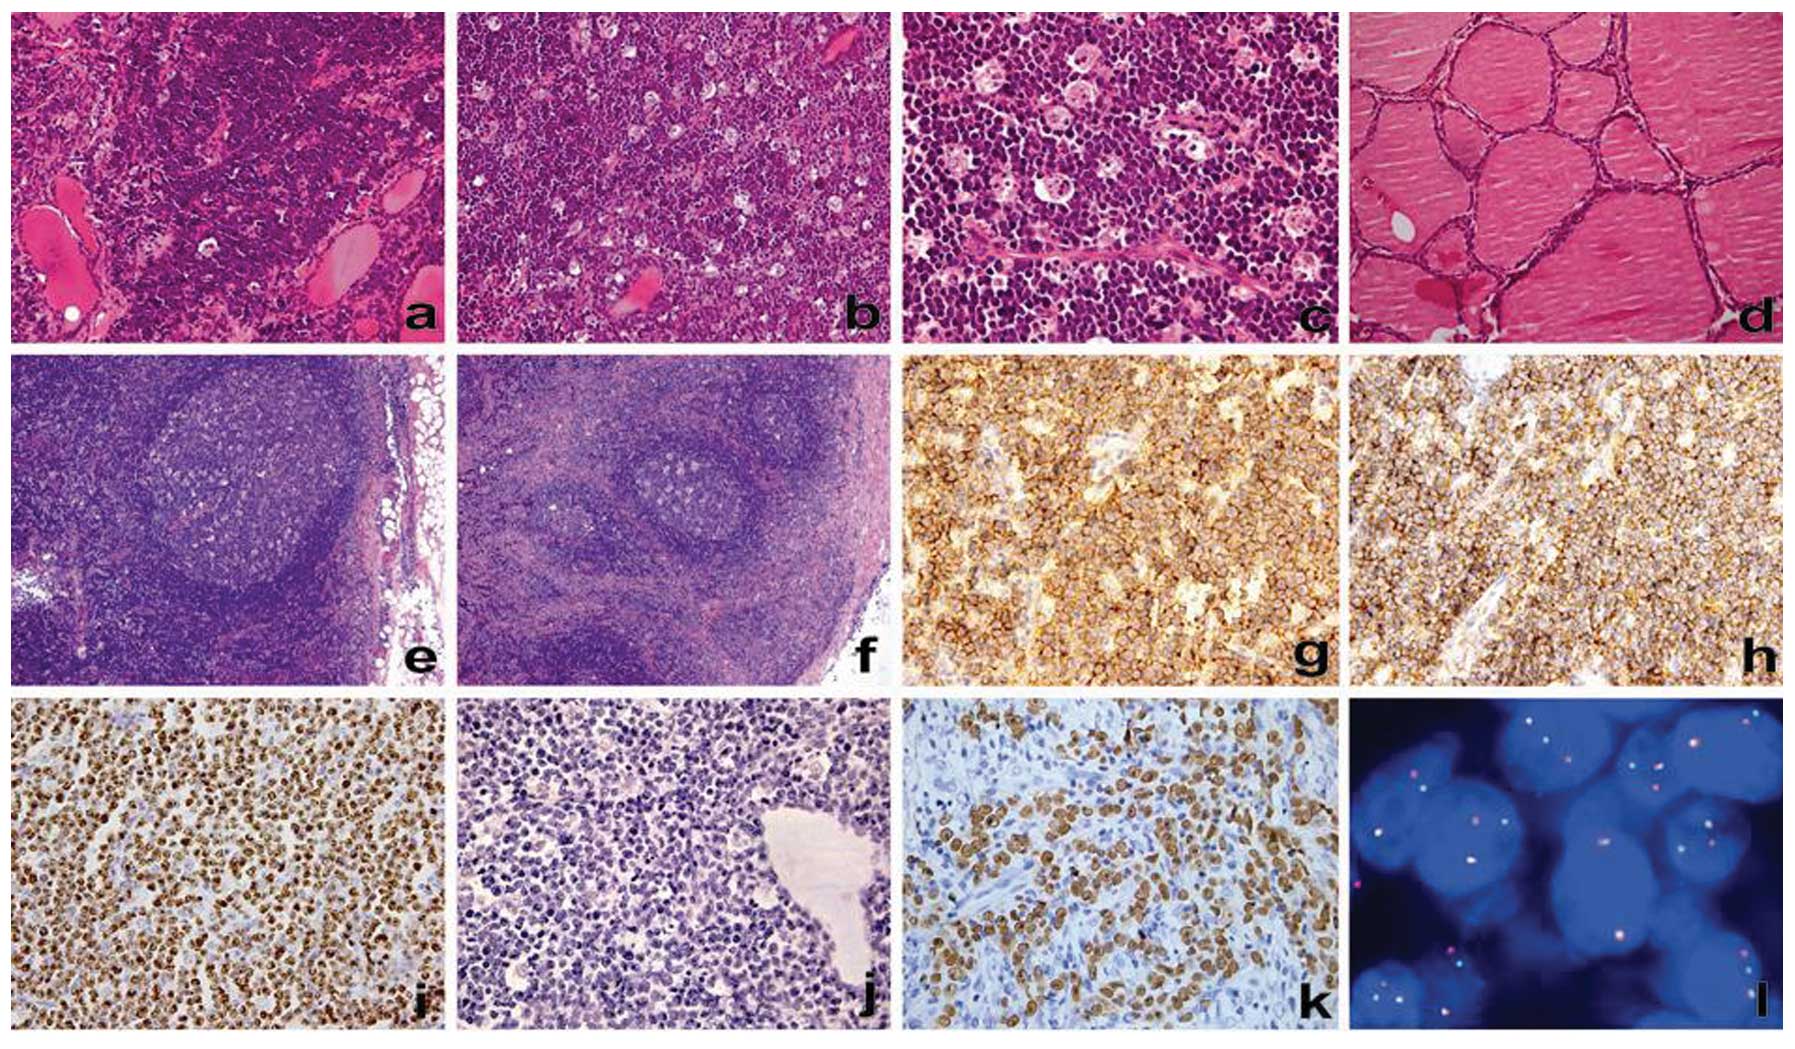

Микропрепараты: Лимфогранулематоз и Нодулярный Склероз